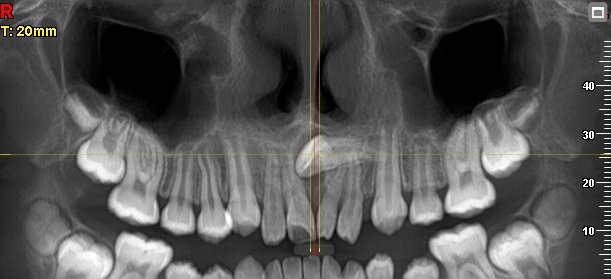

Imágenes 2D-3D Radiografías, Tomografías DENTAL, ATM, SPN, OIDO

Nuestra tecnología Cone Beam 3D permite visualizar estructuras óseas y dentales con alta definición, favoreciendo diagnósticos exactos y resultados clínicos confiables.

Un examen de tomografía computarizada (TAC) macizofacial es una herramienta diagnóstica esencial en la medicina dental y maxilofacial. Este procedimiento …

Los beneficios del examen de tac macizofacial para el diagnóstico dental